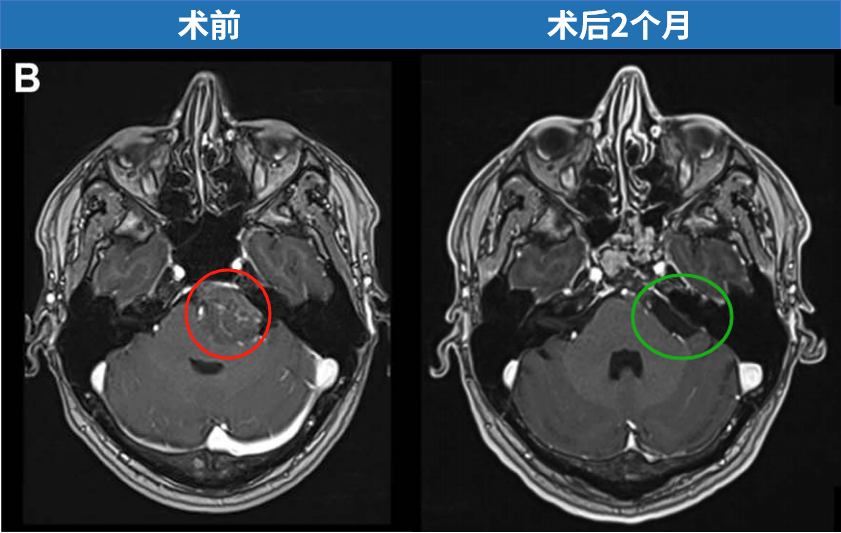

33岁男性患者诺亚持续感觉后脑勺隐痛,检查发现颅底岩斜区存在29×38×38毫米脑膜瘤。该病变挤压脑桥区域,但未引起继发性脑积水,仅表现为普通头痛症状,临床表现具有隐匿性。

诺亚术前影像显示左侧岩斜区脑膜瘤,呈不均匀强化特征。

最终,在INC福教授制定的个体化手术策略下,从术前栓塞、入路选择到手术实施,无需开颅操作,仅通过右侧单鼻孔入路,使用内镜技术成功全切肿瘤。术后脑干复位良好,未出现脑脊液漏及新发神经功能障碍,术后第一天患者可下床活动,术后一周顺利出院。关闭术腔时,采用腹部脂肪填塞硬膜内腔及蝶窦,并缝合鼻黏膜,表面覆盖硅胶片保持湿润;硅胶支架留置4周后取出。